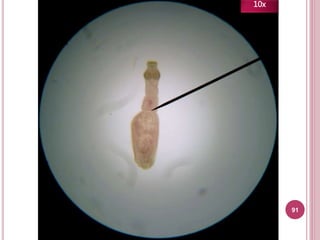

91

10x

Características

 Útero sacular

 Poro genital anterior

Tiene útero

sacular (¡Parece

un saco!)